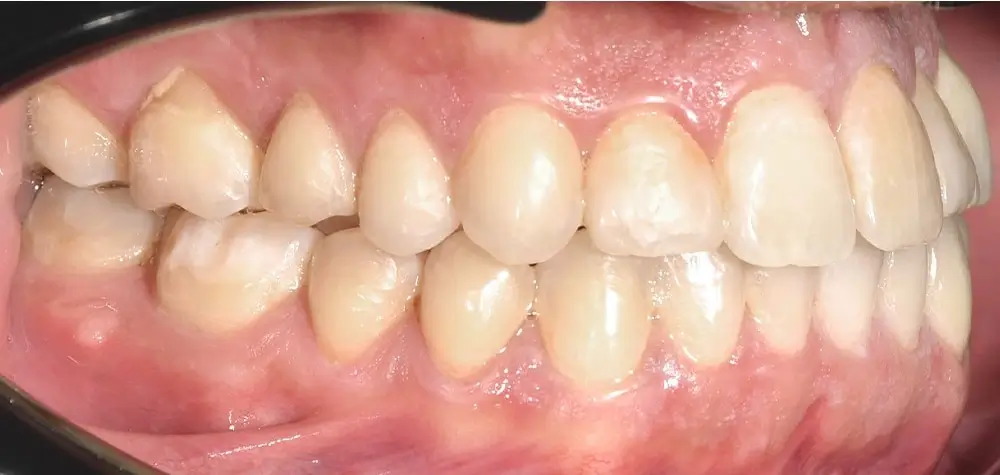

Открытый прикус - Кейс 3

Эффективность устранения дефекта прикуса посредством элайнеров FlexiLigner.

Результаты лечения